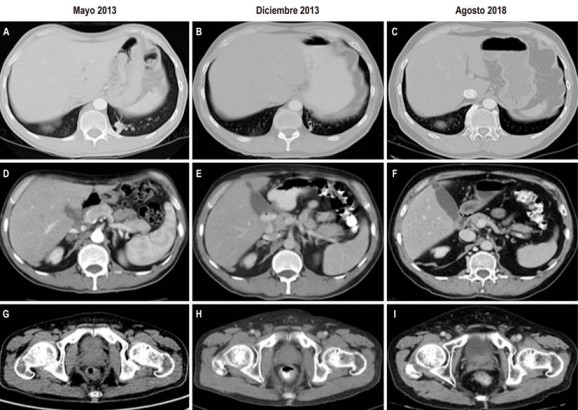

Se realizó biopsia excisional de un ganglio axilar derecho para descartar otro primario, el cual confirma compromiso metastásico a distancia por carcinoma escamocelular del canal anal, con desdiferenciación sarcomatosa. Se hizo el diagnóstico de carcinoma escamocelular del canal anal en estadio IV por T4N2M1 (American Joint Committee on Cancer, versión 7) 9. A pesar de la extensa enfermedad a distancia, teniendo en cuenta el buen estado general del paciente y con miras a brindarle la máxima respuesta posible, se decidió brindar el tratamiento que se reserva para estadios más tempranos: quimiorradioterapia concomitante con mitomicina C 10 mg/m2 días 1 y 29 y 5-fluorouracilo 1000 mg/m2/día en infusión continua los días 1 a 4 y 29 a 32 de la radioterapia. Recibió este tratamiento entre el 20 de agosto y el 05 de octubre de 2013, sin toxicidad limitante. Se obtuvo respuesta clínica completa en canal anal y por tomografías una respuesta parcial dada por disminución mayor del 30% del conglomerado ganglionar en la estación IV izquierda y axilar derecha, resolución del componente ganglionar mediastinal, disminución del tamaño de las lesiones pulmonares, resolución de algunas adenopatías abdominales y disminución del tamaño de las lesiones de la glándula suprarrenal derecha (Figura 2).

Ante la buena respuesta obtenida se decidió continuar tratamiento sistémico con el mismo régimen de quimioterapia de mitomicina C + 5-fluorouracilo, con monitorización hematológica y renal estrecha. El paciente completó 6 ciclos el 10 de octubre de 2014 y desde entonces se dejó en seguimiento. Las tomografías de reevaluación de fin de tratamiento mostraron respuesta pulmonar, ganglionar axilar y cervical completa, persistiendo solo algunas adenomegalias retrocrurales y retroperitoneales izquierdas residuales y estabilidad de las lesiones en la glándula suprarrenal derecha. Desde entonces ha continuado en seguimiento clínico e imagenológico y hasta el control de agosto de 2018 permanece con dichas lesiones estables, sin evidencia de progresión de la enfermedad (Figura 2).